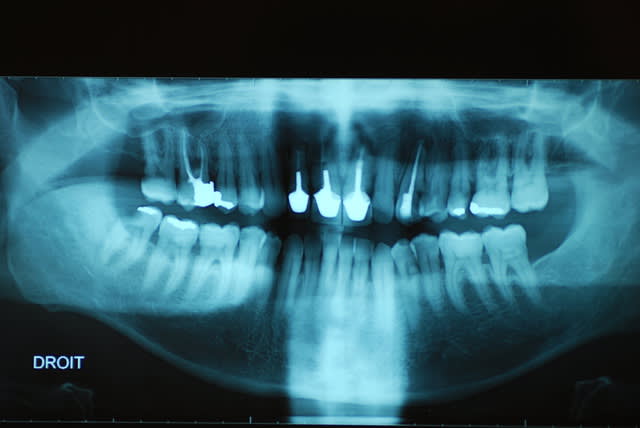

Je viens de revoir le patient et je peux vous apporter quelques précisions ainsi que des photos( désolé si la qualité n'est pas parfaite).

Patient de 45 ans, fumeur, motivé mais ne pouvant se payer d'implants.

Il a déjà vu plusieurs confrères qui lui ont proposé uniquement ( selon ses dires) une solution implantaire pour 12-11-21-22-23. Il souhaite du fixe...

En ce qui concerne la paro, la 12 est en mobilité stade 2, la 22 en stade 1 les autres étant non mobiles. Le sondage de 12 à 22 est de 3 mm, sauf en mésiale de 12 ( 6mm). La gencive est inflammatoire ( logique à la vue de l'inadaptation des couronnes, et des caries radiculaires).

Je pense lui proposer la solution du bridge avec 13,11,21,22, 24,25., même si la 13 est saine... Je prévoyais de reprendre l'endo de 22 mais la taille du tenon et sa longueur m'ont refroidi, peut être qu'une chir endo et obturation à rétro serait plus appropriées... Je prévois bien sur un surfaçage ainsi qu'un assainissement paro, une fois le bridge provisoire en place.

Tu as surtout un gros chantier paro à gérer. Et je ne pense pas que le tenon de la 22 soit si difficile à descendre, accessoirement l'endo de la 11 est aussi à revoir ( et là le tenon semble plus maousse ).

Essai de tout déposer, et améliore les endos, puis provisoires issues d'un wax-up pour simuler l'esthétique , ajuste ça comme il faut et attaque toi a la paro et à l'hygiène déplorable de ton patient......pas de traitement si pas d'hygienne.... Alors des implants dans ces conditions c'est suicidaires.